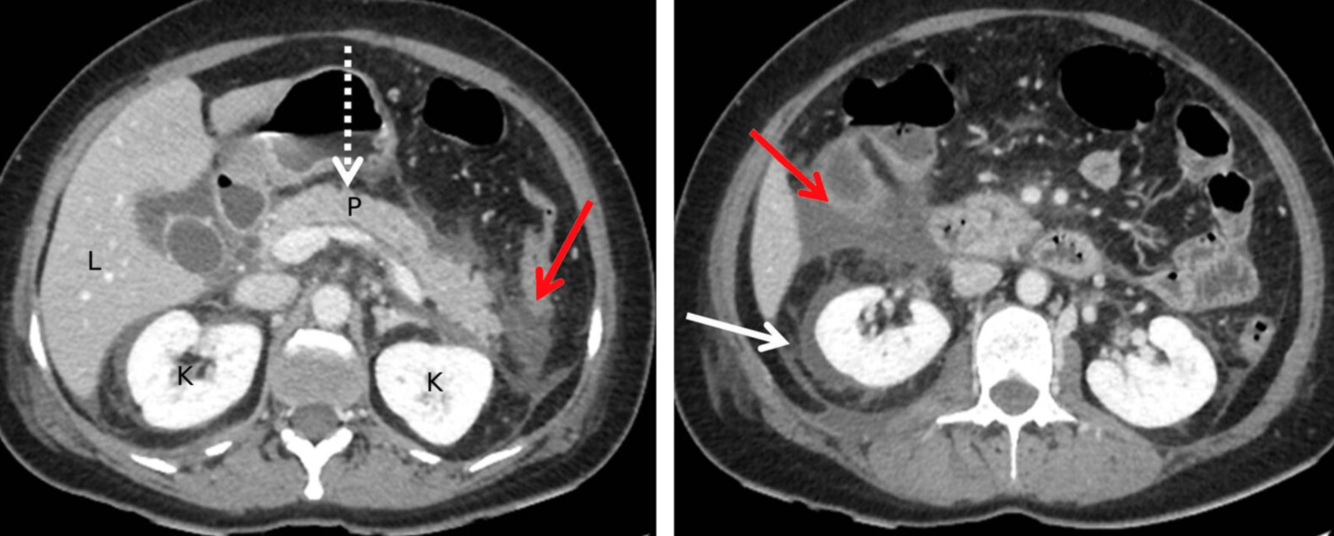

TDM de l’abdomen (avec produit de contraste ; plan axial)

Une collection liquide péripancréatique aiguë homogène non encapsulée (APFC) sans composants solides est visible. L’aspect est caractéristique de la pancréatite interstitielle aiguë (non compliquée). Un échouage liquidien et graisseux peut être observé en avant du pancréas ainsi que dans les espaces pararénaux (flèches rouges). Il existe également du liquide périrénal (flèche blanche). Le tissu pancréatique (flèche en pointillés ; P) est rehaussé de manière homogène, sans signe de nécrose tissulaire.

Les APFC peuvent être uniques ou multiples et se développent généralement au début de la pancréatite aiguë. La persistance pendant plus de 4 semaines augmente la probabilité de développement d’un pseudokyste.